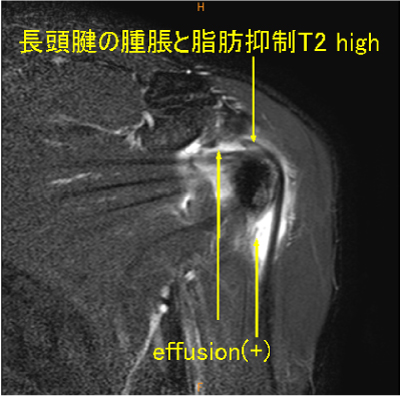

MRI所見

Hidden lesion症例(長頭腱亜脱臼、肩甲下筋腱損傷)

Hidden lesion(長頭腱亜脱臼+肩甲下筋腱断裂), 長頭腱亀裂